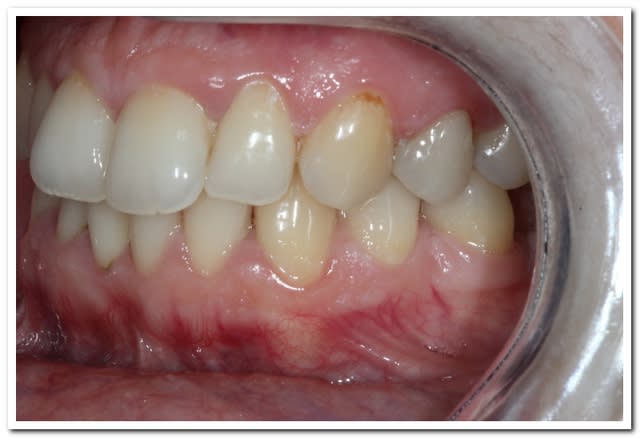

Donc une jolie pulpite avec une restauration intra-pulpaire foulée au pouce.

Endo - RMIPP - Cerec